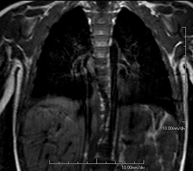

Prova diagnòstica no invasiva que consisteix en l'obtenció d'imatges d'alta definició anatòmica del mediastí mitjançant l'ús d'un camp electromagnètic i ones de ràdio (amb un emissor i un receptor). No utilitza radiació ionitzant. El mediastí és la part central de la caixa toràcica que inclou el tim, els grans vasos (aorta toràcica, vena cava inferior i superior, etc.), el cor, la tràquea i els bronquis principals, els ganglis limfàtics mediastínics i hilars, l'esòfag, etc. Està especialment indicada en lesions mediastíniques per diferenciar si són quístiques o sòlides, en el diagnòstic diferencial de les lesions del mediastí anterior, etc. De vegades s'ha d'emprar contrast paramagnètic (Gadolini) per completar l'estudi. - RM Tòrax

Prova diagnòstica no invasiva que consisteix en l'obtenció d'imatges d'alta definició anatòmica del tòrax mitjançant l'ús d'un camp electromagnètic i ones de ràdio (amb un emissor i un receptor). No utilitza radiació ionitzant. Està indicada en aquelles lesions pulmonars en les quals s'ha de descartar si hi ha infiltració del mediastí o de la paret toràcica, per diferenciar si una lesió toràcica és sòlida o quística, etc. En alguns casos caldrà emprar contrast paramagnètic (Gadolini) per completar l'estudi. - RM de Paret Toràcica